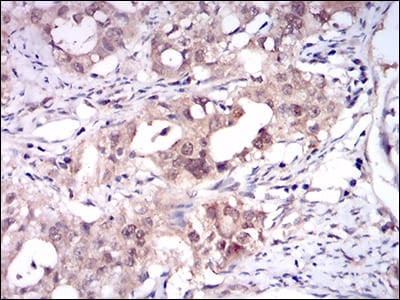

分类: 科研抗体货号: 30534别名: OC3应用: IHC反应种属: Human

分类: 科研抗体货号: 30533别名: OC3应用: IHC,IF反应种属: Human

分类: 科研抗体货号: 30517别名: CASH; FLIP; MRIT; CLARP; FLAME; Casper; FLAME1; c-FLIP; FLAME-1; I-FLICE; c-FLIPL; c-FLIPR; c-FLIPS; CASP8AP1应用: IHC反应种属: Human